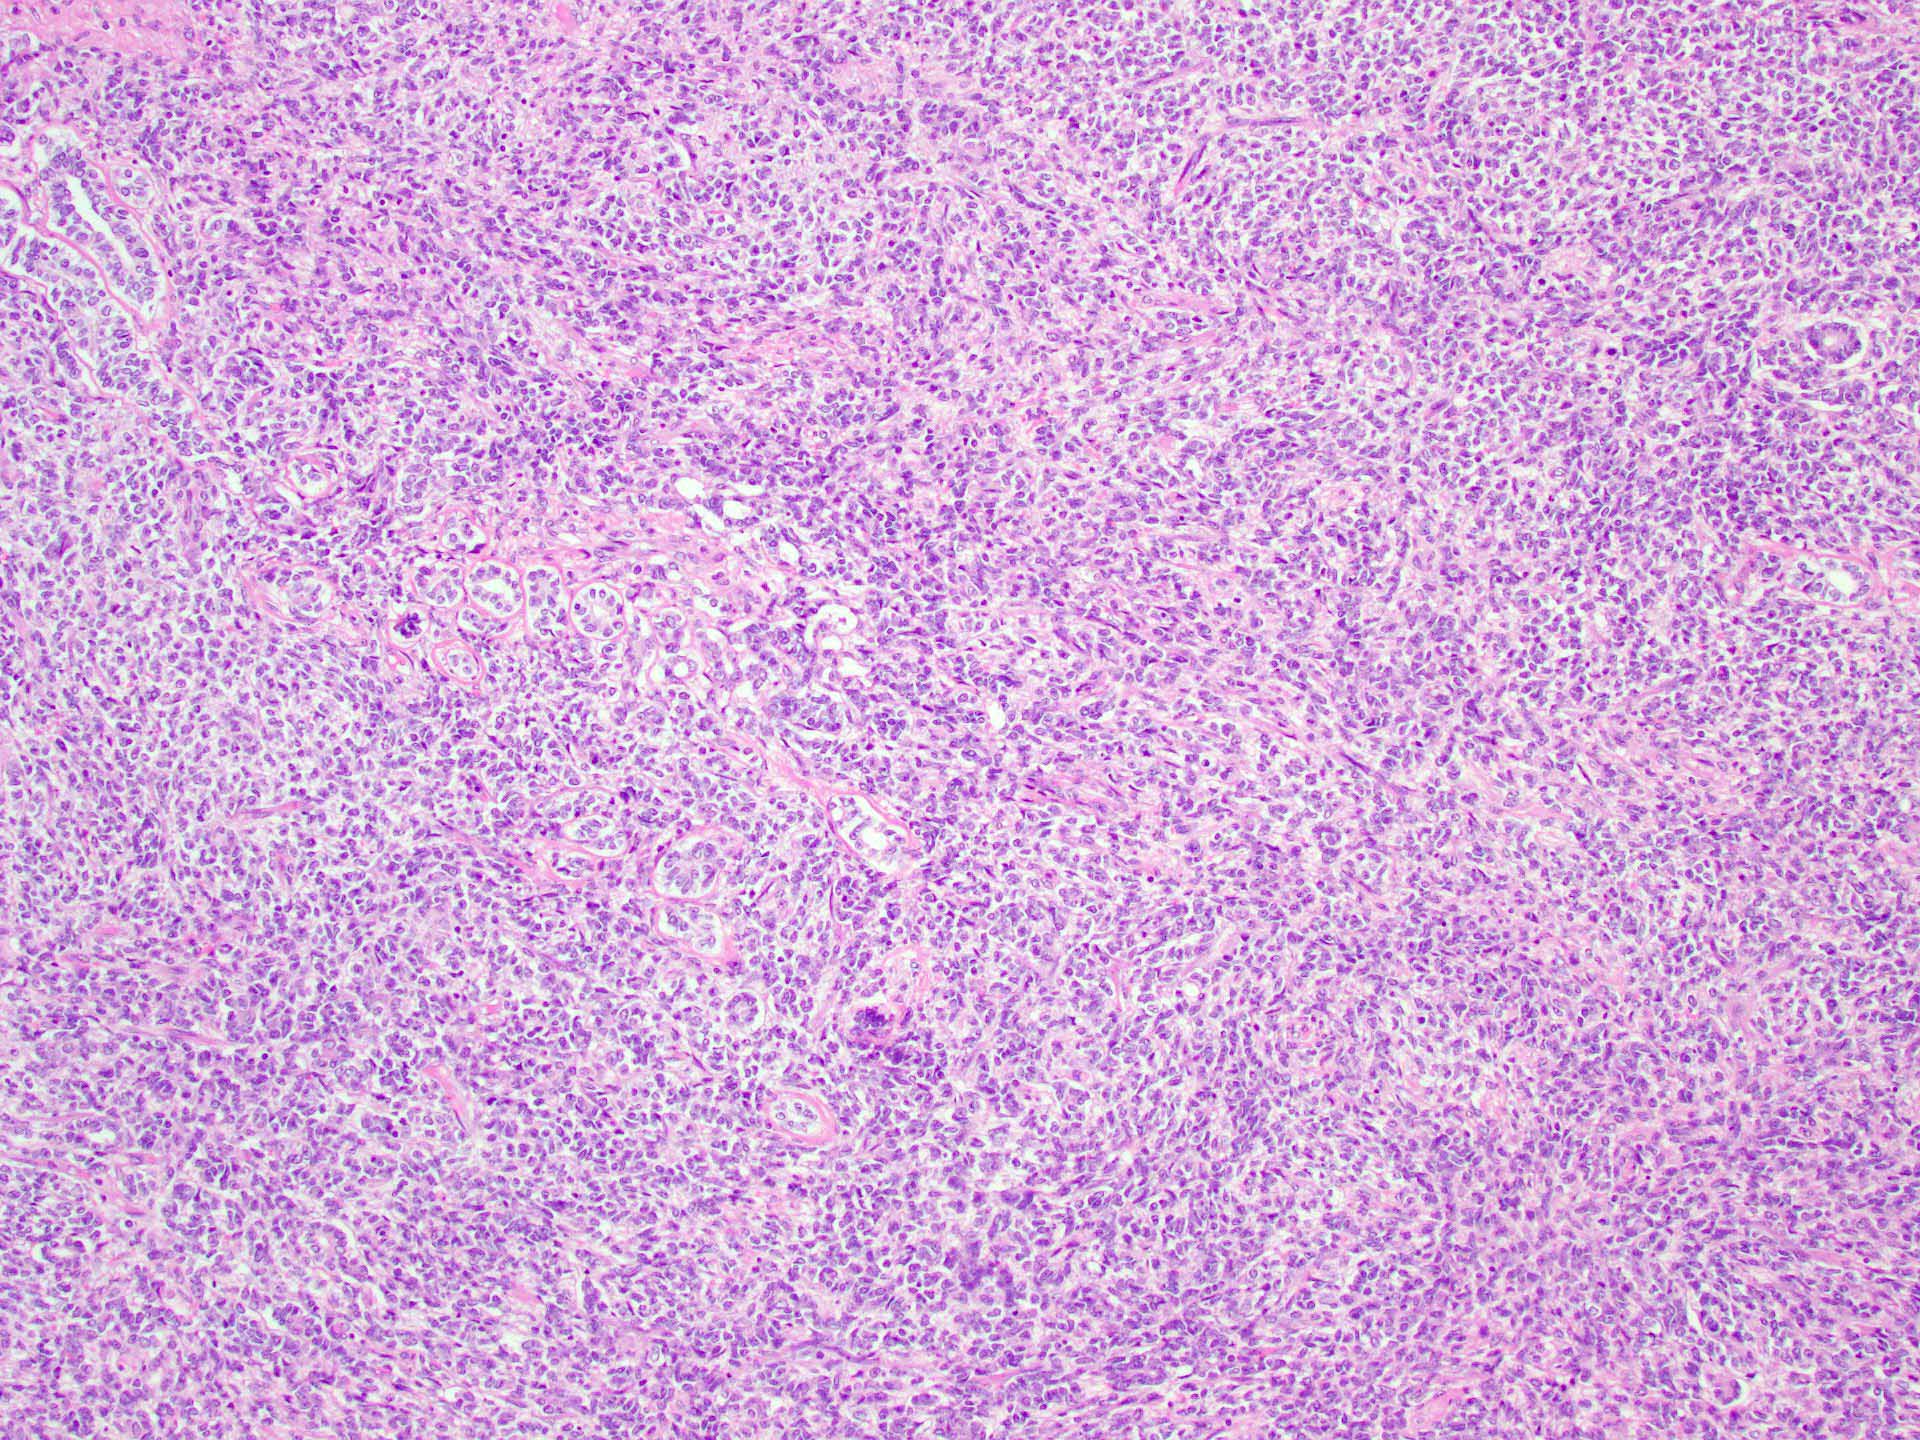

Microscopic (histologic) description

- Tubular pattern (most common and usually present at least focally) with solid or hollow tubules

- Cuboidal or columnar cells

- Bland oval to round, monotonous nuclei

- Pale cytoplasm

- Lipid rich or oxyphilic variants may be associated with Peutz-Jeghers syndrome

- Other patterns: trabecular, diffuse, alveolar, pseudopapillary, reniform, pseudoendometrioid, spindled

- Absent to very rare Leydig cells

- Pathologic features predictive of malignant behavior include 5 mitoses per 10 high power fields, severe cytologic atypia, necrosis and size > 5 cm

- Reference: Am J Surg Pathol 2005;29:143

Microscopic (histologic) images

A 40 year old woman is seen in the clinic with complaints of irregular uterine bleeding and pelvic fullness. Transvaginal ultrasound shows a 9 cm right ovarian mass. The mass is surgically removed and a pathologic examination shows the features in the picture above. The mass is positive for inhibin and SF1. The tumor is negative for EMA, PAX8, MelanA and chromogranin. In which of the following general categories does this tumor belong?

C. Pure sex cord tumor. Sertoli cell tumor is a pure sex cord neoplasm of the ovary composed of Sertoli cells most commonly arranged in a tubular pattern. Sertoli cells are positive for inhibin and SF1. Answer D is incorrect because no Leydig cells, which are positive for MelanA and are stromal in nature, are present. Answer B is incorrect because the tumor is negative for neuroendocrine markers. Answer A is incorrect because the tumor is negative for EMA and PAX8.